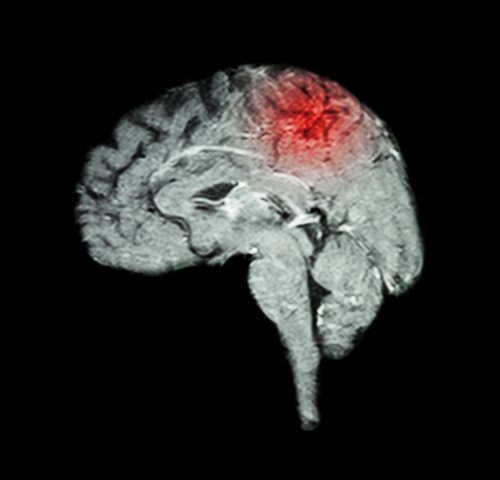

A dor central pós-AVC ocorre devido ao acometimento de regiões do sistema nervoso central envolvidas no processamento de informações sensitivas. A dor geralmente localiza-se nos segmentos do corpo onde há presença de comprometimento motor e sensorial.